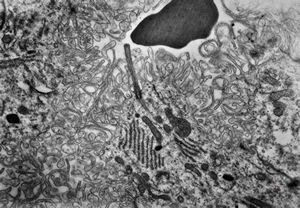

F,50y. | progressive multifocal leukoencephalopathy- viral particles in a glial cell

F,50y. | progressive multifocal leukoencephalopathy- viral particles in a glial cell

F,50y. | progressive multifocal leukoencephalopathy- viral particles in a glial cell